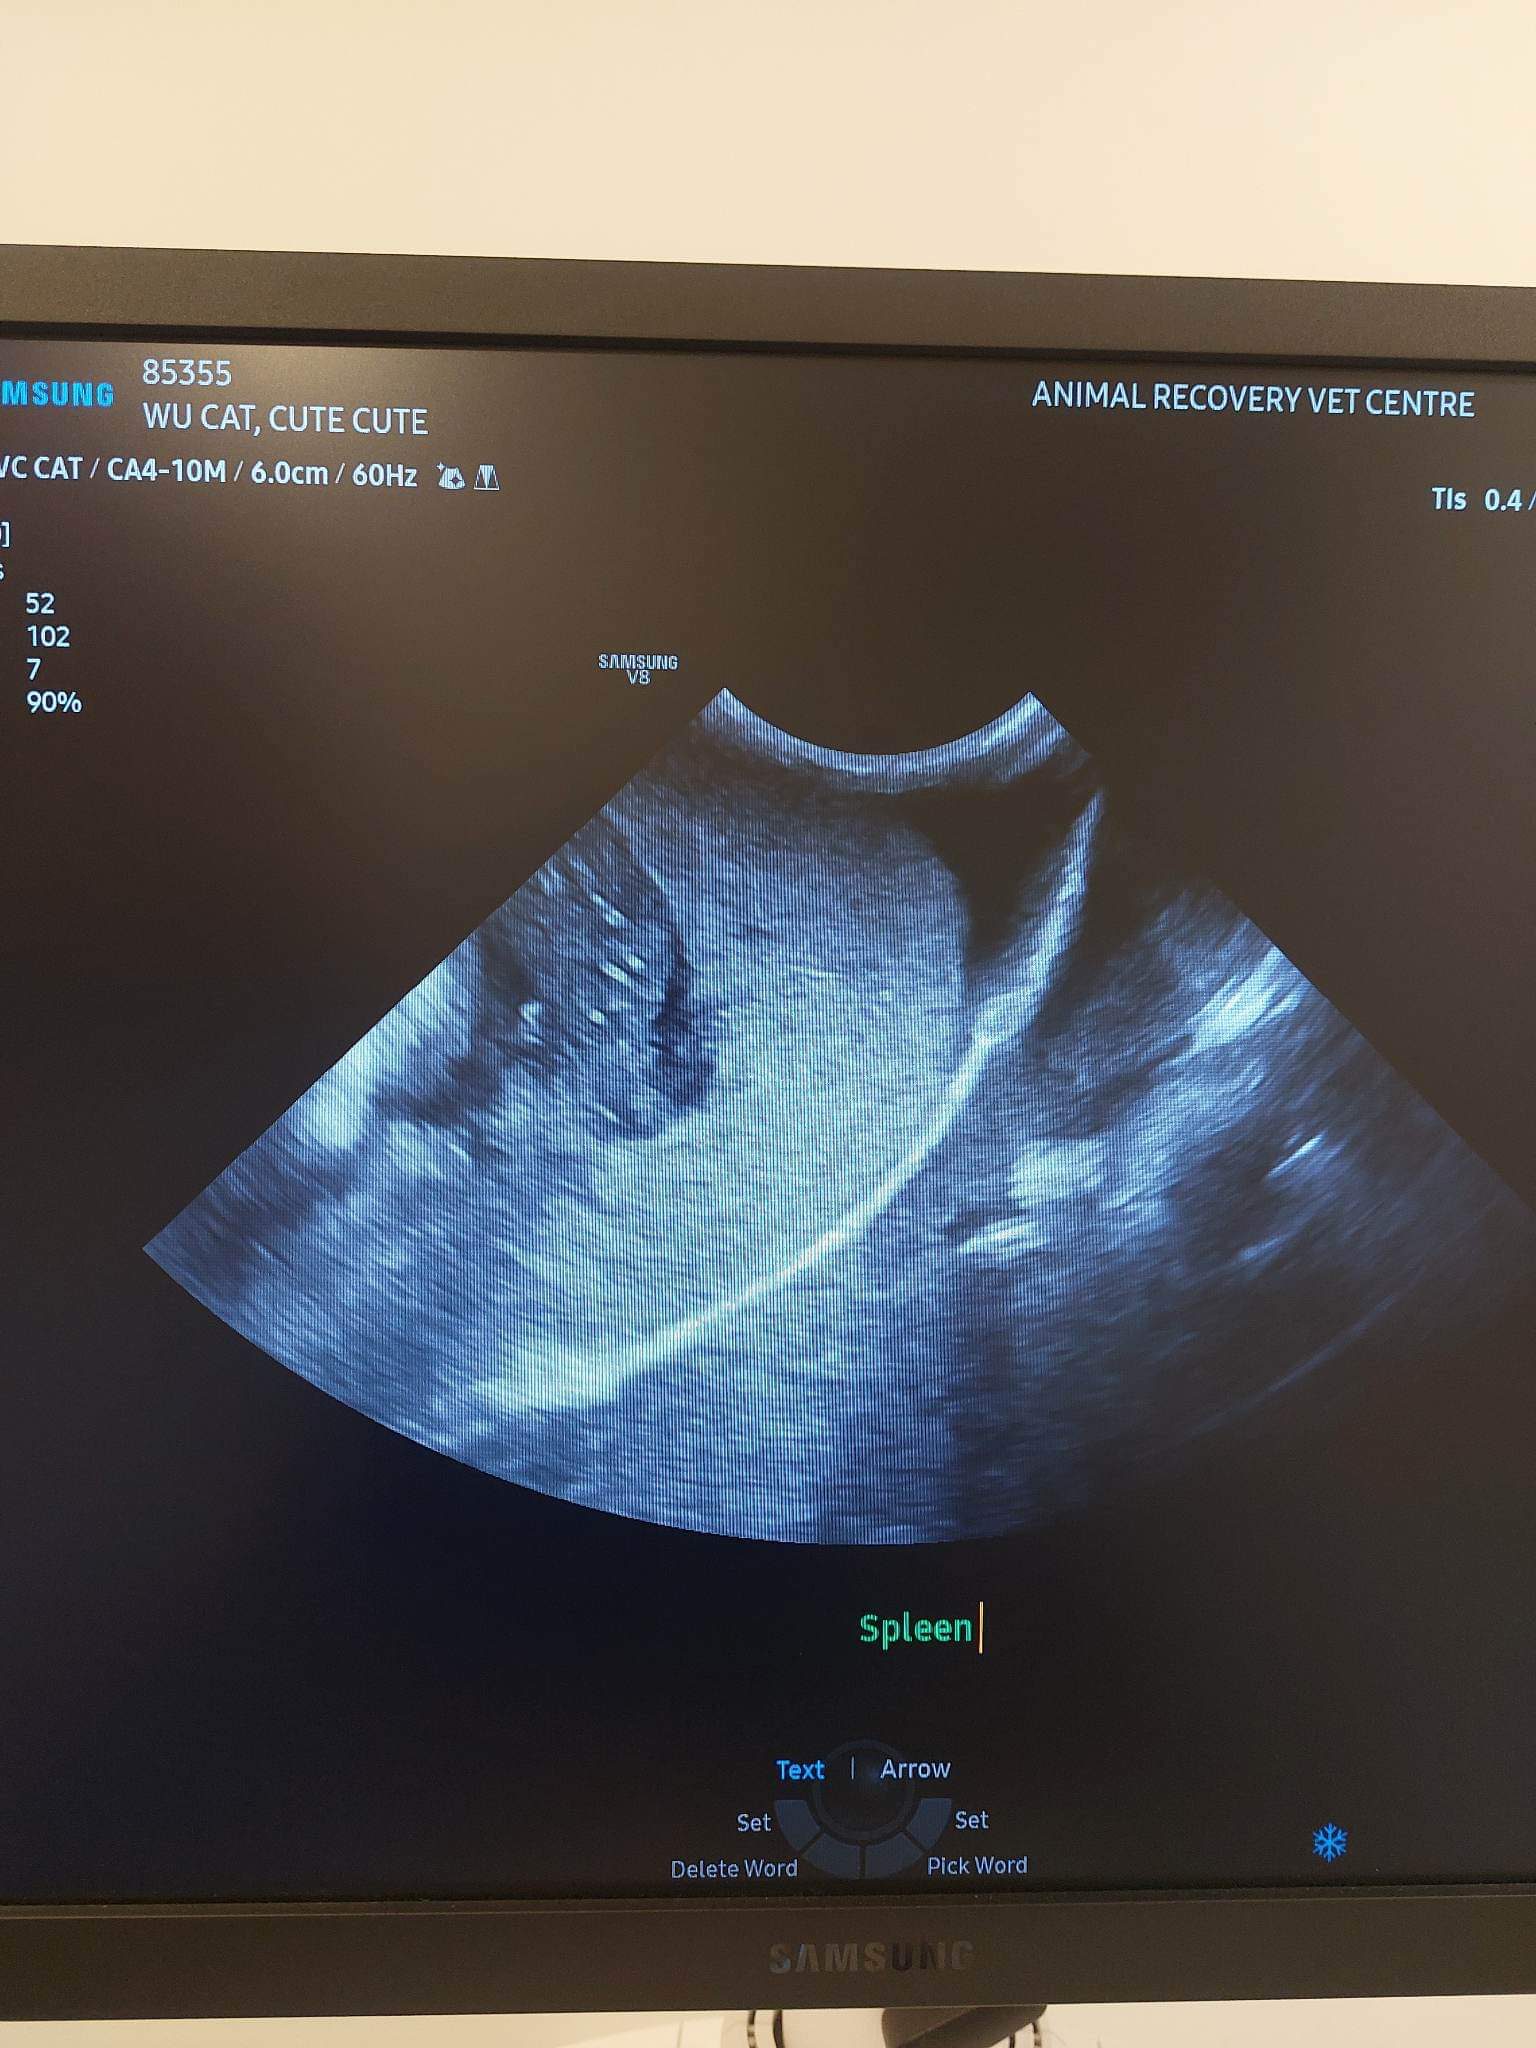

1040am: Dr yeumee bring cute in to shave a bit and get ready for u/s

U/s: core findings: highly is lymphoma. Super enlarged spleen (only good news is no sign of showing bleeding fr spleen yet), enlarged liver. Multiple masses in abdomen, all highly point to cancer (I’ll start pred 0.5mg/kg per feed, ie 1.25mg x twice a day) – pred will help in boosting rbc also. Intestine thickening also.

Fluid in chest and lungs- not drawing out not a lot yet.